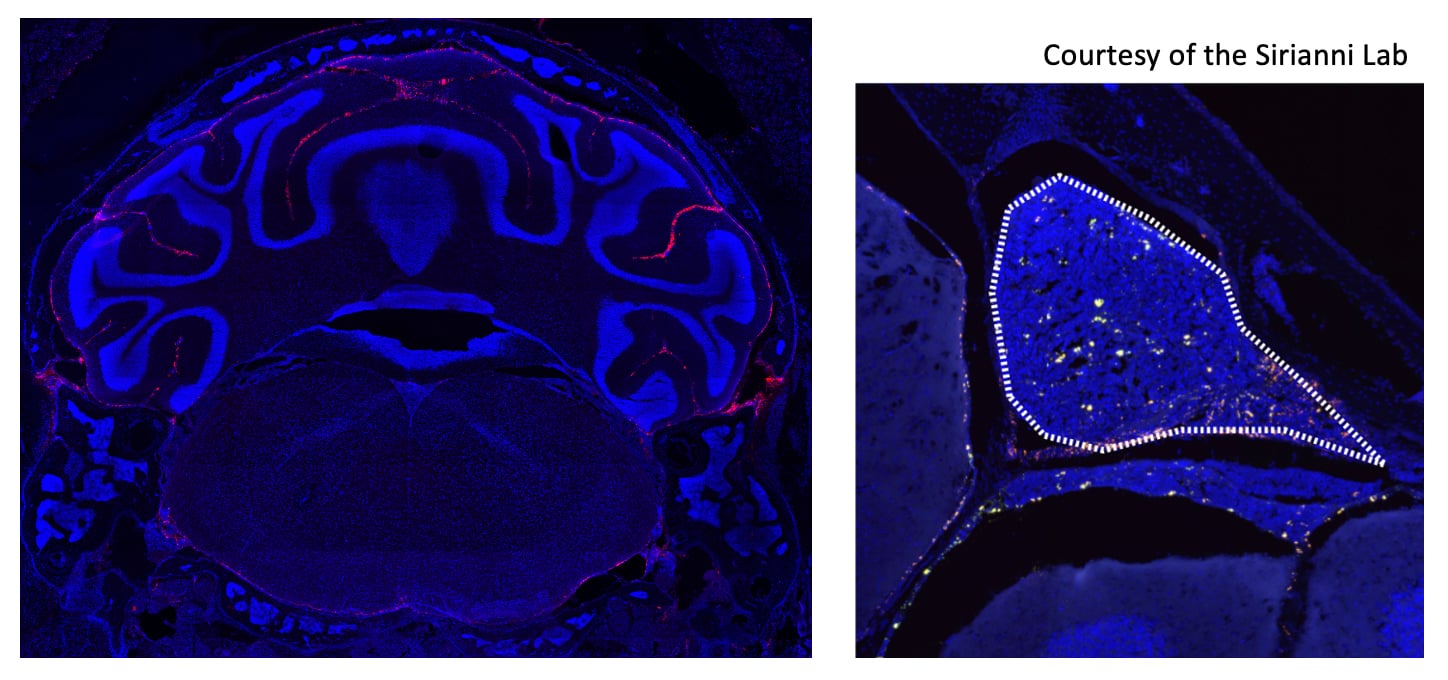

Figure 2 below illustrates how nanoparticles that have been delivered to the subarachnoid space reach their target tissue.

Figure 2:   Left: Nanoparticles (red) reached all CSF-exposed surfaces of cerebellum. Right: Nanoparticles (yellow) within the subarachnoid space penetrated a focal tumor metastasis (outlined in white). Cell nuclei are stained in blue in both images.